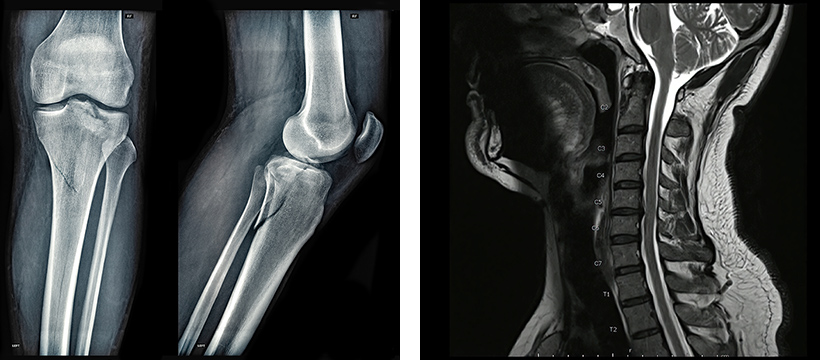

頚椎症性脊髄症の術後も症状が残存。脊髄腔内に2,500万個を3回投与。歩行距離が約17倍に改善し、膀胱直腸障害も改善。

必要に応じてMRI検査を予約。現在の状態を正確に把握します。